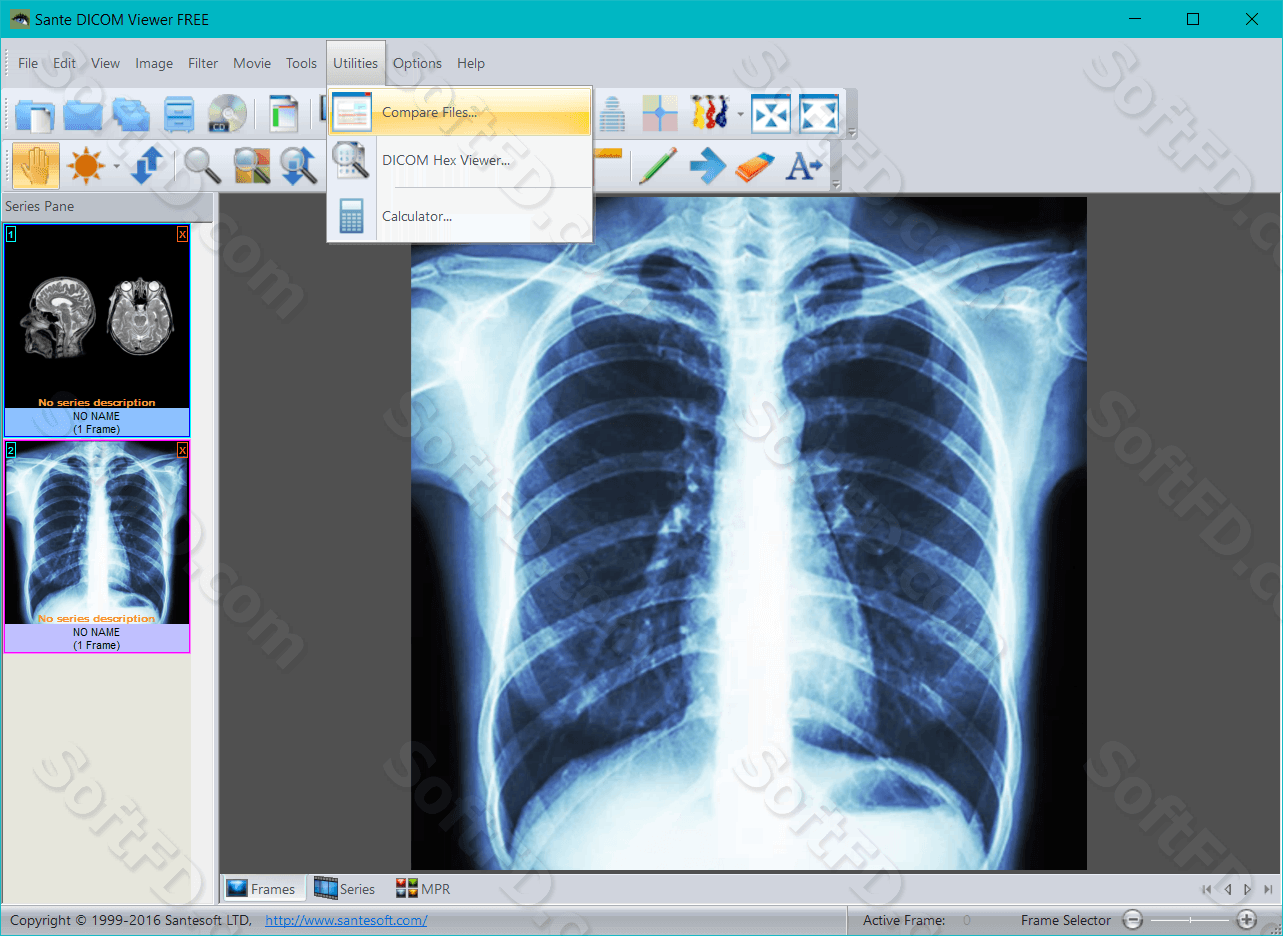

Лазерная камера сетевая для печати изображений на пленке стандарт dicom